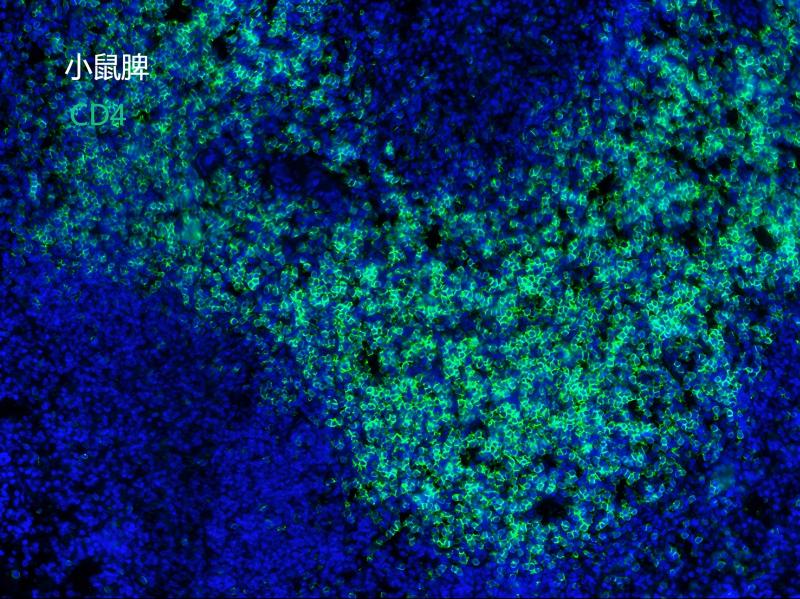

CD4 (Y0610) Rabbit mAb

HL18419